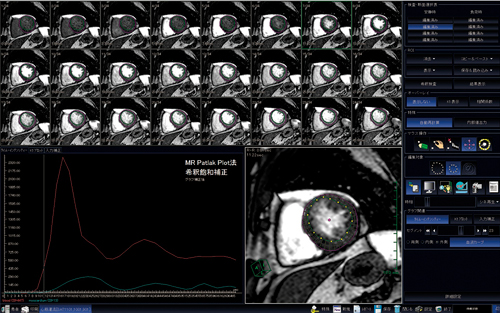

この定量方法は,左心室の血液入力カーブと心筋出力カーブに対して2コンパートメントモデルに基づいたパトラック解析を行い,心筋血流の定量値を算出するというものである。

撮像は,従来の心筋負荷時と安静時の撮像に加えて,同条件にて10倍希釈造影剤による補正データを撮像する。3つの撮像データをすべて読み込み,スライス,フェーズそれぞれにおいて心外膜・心内膜・血液領域のROIをトレースする(図4)。ROIのトレースが終わると,定量解析結果が安静時・負荷時・予備能がBull’s eye表示される(図5)。スライス数で見ると非常に多い枚数のトレースの確認と修正を必要とするが,修正も簡便に行えるようになっており,比較的覚えやすく,慣れやすい処理であると感じている。

図4 ROIのトレース画面